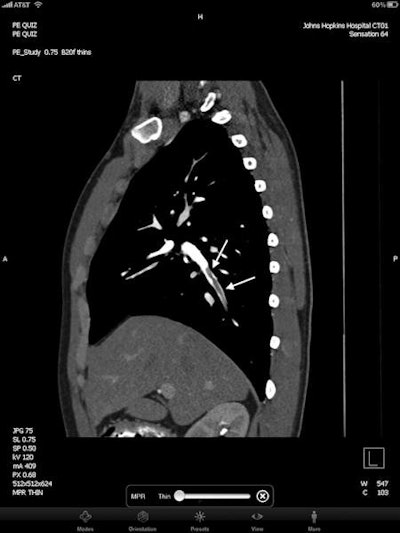

| Axial image (top) and sagittal multiplanar reconstruction (bottom) from contrast-enhanced MDCT viewed on the iPad. Arrows show right lower lobe segmental pulmonary embolism. All images courtesy of Dr. Pam Johnson. |